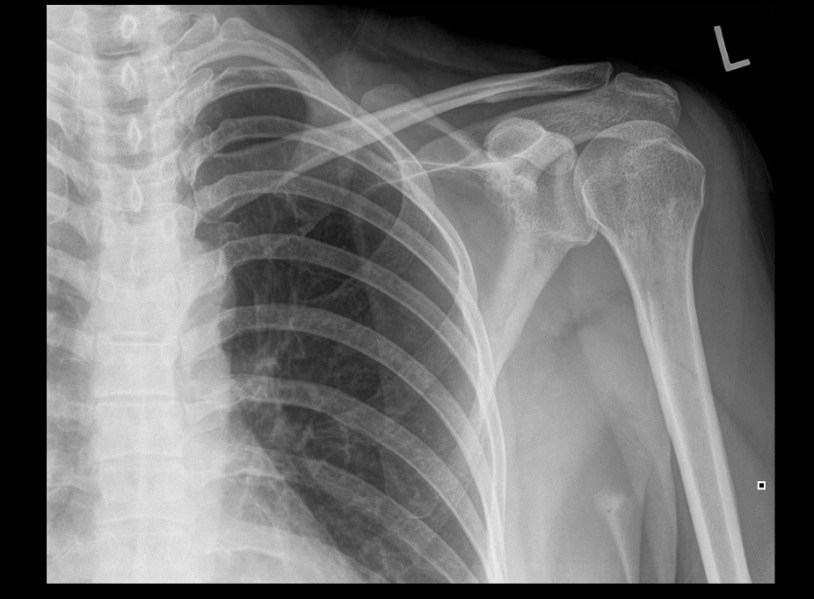

What projection position is this image?

AP Shoulder with Neutral Roation, Left